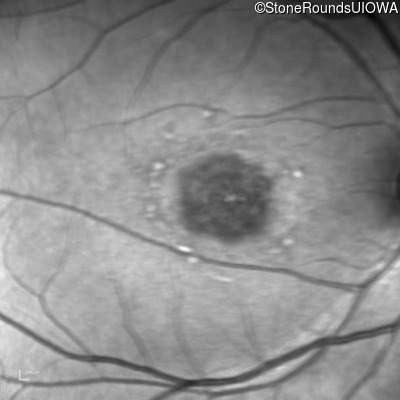

Optical Coherence Tomography - Right - 20/125 -1

Exemplar / OCT Stack